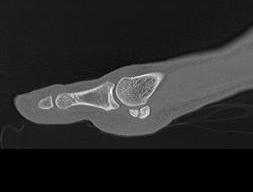

CT demonstrates irregular borders consistent with fracture of tibial sesamoid